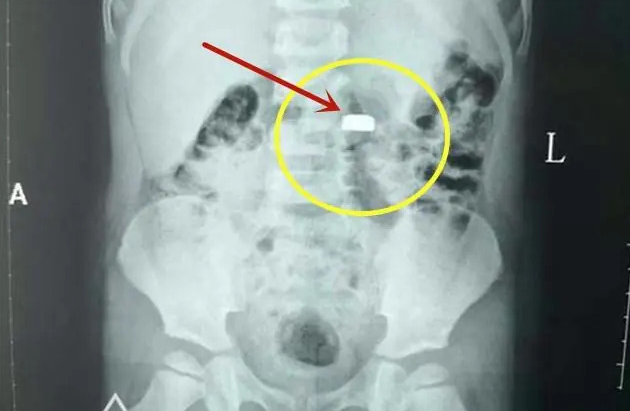

ส่งโรงพยาบาลด่วนที่สุด: แจ้งหมอทันทีว่าสงสัยว่าลูกกลืนถ่าน เพื่อรับการเอกซเรย์และส่องกล้องออกทันที